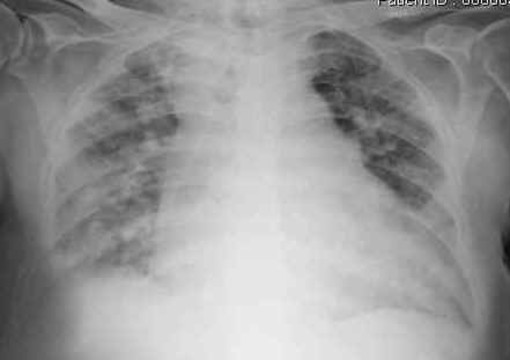

in cui non solo si indicavano le principali malattie prodotte dall’inquinamento ambientale ma anche la percentuale ingravescente di tumori ed altre malattie con l’avvicinarsi ad una causa d’inquinamento come la discarica, e lo stesso si può dire anche per gli inceneritori e le centrali a carbone.

Nel febbraio 2011 è uscito un interessante articolo sul Pais Semanal ‘Respirare pregiudica seriamente la salute’ in cui si parla proprio dei danni alla salute prodotti dalle polveri ultrafini (un milionesimo di millimetro) che attraverso i capillari degli alveoli passano nel circolo sanguigno e sono proprio le microparticelle che la Centrale TirrenoPower non controlla nelle tonnellate di polveri che escono dalle ciminiere.

Per quanto riguarda la provincia di Savona, l’Ordine dei Medici ha inviato l’anno scorso, a tutti i medici, con la sua rivista, un accurato studio scientifico in cui si evidenzia il tasso di morbilità-mortalità annuale prodotto dall’inquinamento, cui contribuisce notevolmente la Centrale TirrenoPower, superiore a quello delle altre province liguri ed uno dei più alti in Italia.